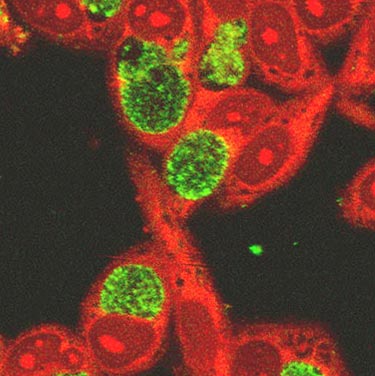

Рис. 1. Збудники хламідіозу Chlamidia trachomatis всередині клітин епітелію кон'юнктиви очі.

Для проведення даного методу необхідно мати зішкріб ураженої слизової, так як хламідії розмножуються внутрішньоклітинно, де розташовуються у вигляді ретикулярних тілець.